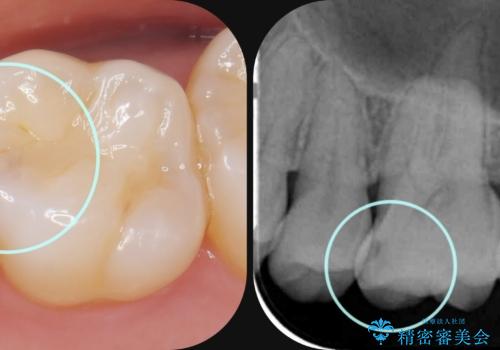

- 幼少期に前歯をぶつけて歯が折れ、神経の治療・クラウン治療を行った。グラつきと見た目の改善を希望して来院されました。

精密な仮歯をいれ、歯周組織を整えるとともにファイバーコア築盛、シェードテイキングを行い見た目に自然なジルコニアクラウンを製作していきます。